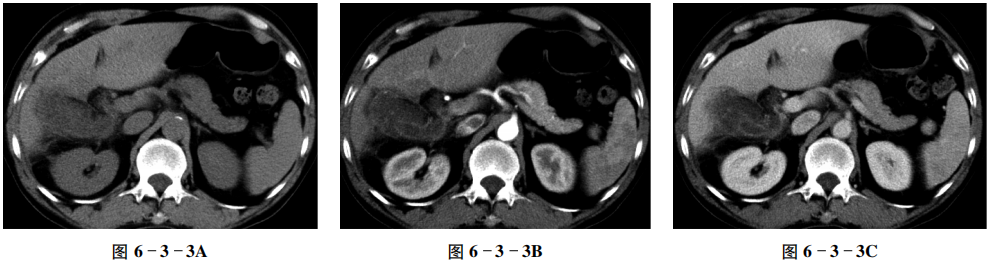

【CT征象】 平扫示胆囊体积明显增大,囊壁不均匀增厚,周围脂肪间隙模糊(图6-3-3A);增强扫描胆囊壁呈多发“串珠状”强化,内见多发线状分隔,呈明显强化,胆囊黏膜线连续,周围肝胆界面模糊(图6-3-3B~D)。

【重要征象】 胆囊壁增厚伴“串珠状”强化。

【CT拟诊】 ① 胆囊癌。② 黄色肉芽肿性胆囊炎。③ 胆囊腺肌症。④ 慢性胆囊炎。

【病理诊断】 黄色肉芽肿性胆囊炎。